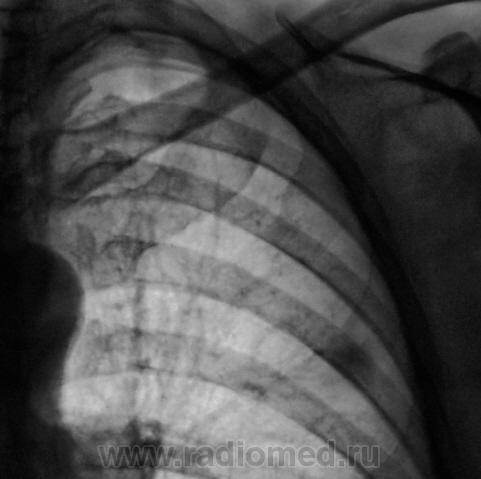

Еще одна "срезка" правой верхушки.

Последняя "срезка" правой верхушки, наряду, с изменениями самой верхушки, поразила значительным "уплотнением" апикальной плевры, чего на других срезах зарегистрировано не было.

Да. Возможно и онкология. А возможно и фиброзные изменения в очаге, плюс свежие т.е обострение. И как всегда вопрос: стандарт в данном случае 7, 8, 9 см или 10,11,12? Возьму на заметку))).

Понятно. Да такая "лучезарная" форма тени скорее наведёт на мысь о онкологии.

Да, слева "лучезарная тенюшка" расценена, как онкология.